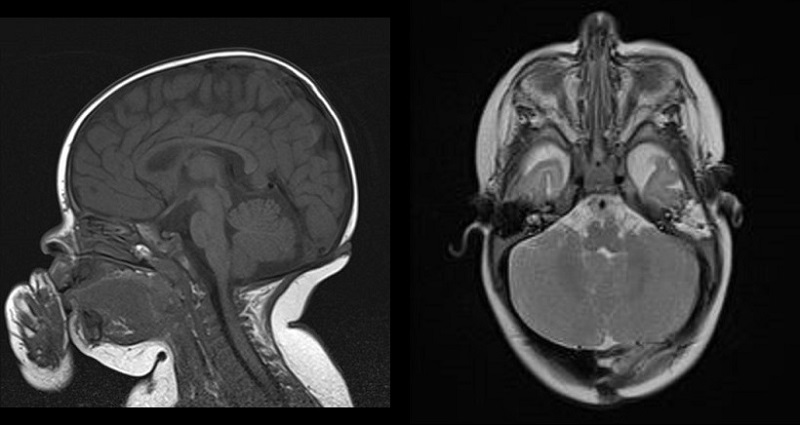

Ante la sospecha de disrafismo craneal, ingresa para estudio y realización de pruebas de imagen. En la resonancia magnética (RM) cerebral se visualizó una lesión dérmica occipital central, levemente lateralizada a la derecha, de aproximadamente 1 cm, con umbilicación central, que se extiende al tejido celular subcutáneo hasta contactar con una pequeña discontinuidad en la calota, próxima al seno transverso derecho, sin contacto con estructuras vasculares intracraneales, compatible con seno dérmico (Fig. 2). La RM de columna vertebral descartó lesiones a otros niveles.

| Figura 2. Trayecto del seno dérmico subcutáneo en resonancia magnética craneal (secuencia T1 sin contraste intravenoso) |

|---|

![]() |